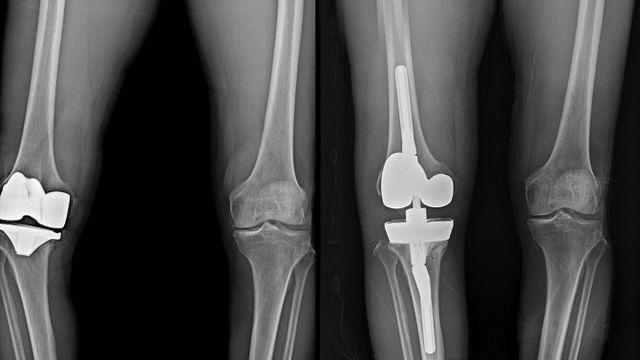

연세사랑병원, 무릎 인공관절 재수술 1천례 달성